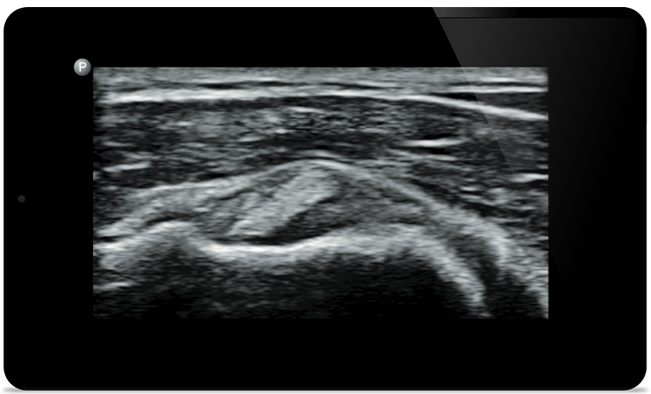

O Lumify ajuda você a ver os detalhes finos em músculos, articulações, ligamentos, tendões e cartilagem para fazer um diagnóstico mais preciso de lesões.

O Lumify pode ajudar a avaliar pacientes da cabeça aos pés, seja fascite plantar, tendinite ou bursite no tendão patelar, ou mesmo instabilidade do ombro no manguito rotador.

A SonoCT reforça o diagnóstico por imagem real do tecido enquanto elimina artefatos aleatórios. Essa tecnologia produz diagnóstico por imagem superior aos convencionais em até 94% dos pacientes.